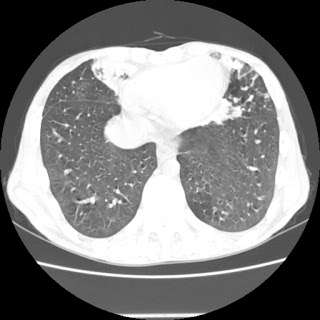

Repeat radiological images: